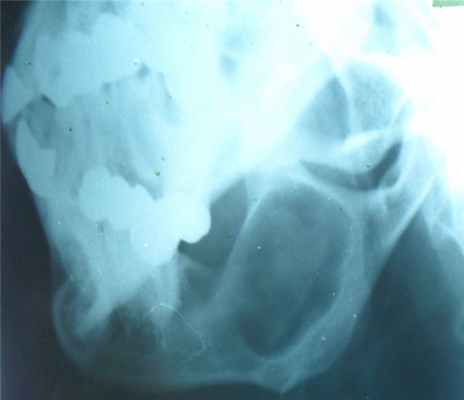

Гигантоклеточная опухоль

(остеобластокластома)

- состоит из клеток 2 типов- многоядерных гигантских и мелких одноядерных,

- поражаются люди в возрасте от 20 до 40 лет,

- локализация бедренная кость - дистальный конец, проксимальный конец б/берцовой кости, дистальный конец лучевой кости. Из плоских костей – тазовые кости и лопатка, очень редкая локализация в позвонках,

- одиночность и изолированность поражения,

- характерно расположение опухоли в эпиметафизраном отделе, который значительно вздут и деформирован, имеет вид крупнобугристого полушария, булавы,

- опухоль доходит до суставного хряща и обрывается,

- растет во всех направлениях, но главный рост происходит вдоль длинной оси кости в сторону с/3 диафиза кости,

- поперечник опухоли может увеличивать нормальный диаметр опухоли в 3-5 раз.

- ячеистый тип - опухоль состоит из отдельных камер, отделенных друг от друга полными и неполными перегородками (мыльные пузыри или неправильные соты),

- корковое вещество раздвигается, вздувается изнутри, истончается, надкостничных наслоений нет,

- при больших опухолях корковое вещество рассасывается и опухоль окружена со всех сторон тонкой скорлупой состоящая из стенок поверхностно расположенных ячеек.

- остеолитический тип – полное отсутствие ячеистого или трабекулярного рисунка, дефект кости вполне гомогенен,

- краевой блюдцеобразный дефект,

- корковый слой на пораженном месте рассасывается, а на границе с дефектом корка заострена, не подрыта и не имеет никаких периостальных наслоений,

- контуры дефекта резкие,

- патологические переломы в 12% случаев.

Доброкачественная гигантоклеточная опухоль кости

Доброкачественные гигантоклеточные опухоли кости обычно возникают у лиц в возрасте от 20 до 30 лет и располагаются в эпифизах и дистальной эпифизарно-метафизарной области. Эти опухоли считаются локально агрессивными. Они продолжают разрастаться, разрушая кость, могут в конечном итоге разрушить остальную часть кости и распространиться на мягкие ткани. Они могут вызывать боль. Эти опухоли печально известны своей склонностью к рецидивам. В редких случаях гигантоклеточная опухоль кости может метастазировать в легкое, даже если она остается гистологически доброкачественной.

Доброкачественные гигантоклеточные опухоли кости при визуализации проявляются как экспансивное литическое поражение. При визуальных исследованиях обнаруживается склеротический ободок –граница между опухолью и нормальным губчатым веществом кости. Необходимо выполнение биопсии. Поскольку гигантоклеточная опухоль кости может метастазировать в легкие, на начальной стадии проводится КТ грудной клетки.